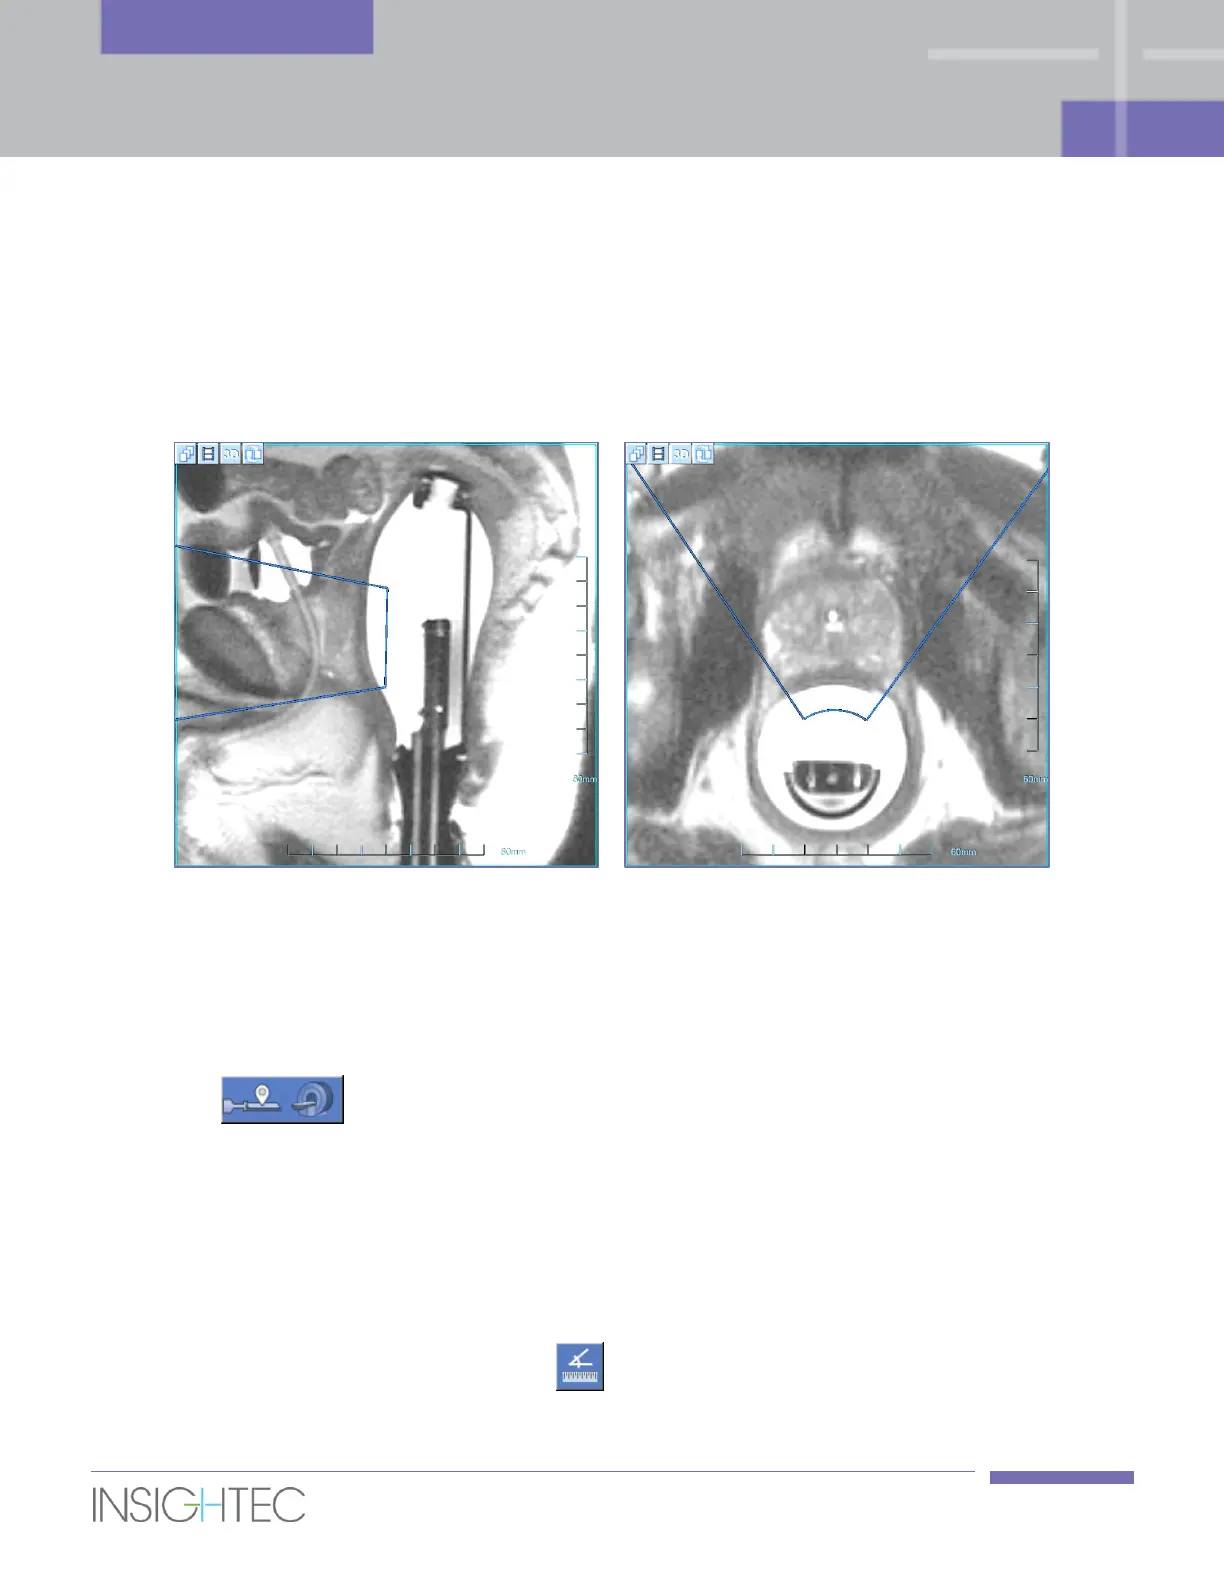

The Treatment Envelope represents the volume that can be reached and treated based on transducer

position, and taking into account mechanical motion and electrical steering capabilities. The Treatment

Envelope is overlaying the scanned Positioning images (see Figure 6-2).

Figure 6-2: Treatment Envelope (blue) displayed on Sagittal Positioning image (left)

and on Axial Positioning image (right)

4. On the Axial Positioning images, verify that the treatment envelope covers the entire designated

region of treatment.

If the treatment envelope does not fully cover the entire designated region of treatment on the Axial

images, use the angle measurement tool to measure the required degree of the probe rotation.